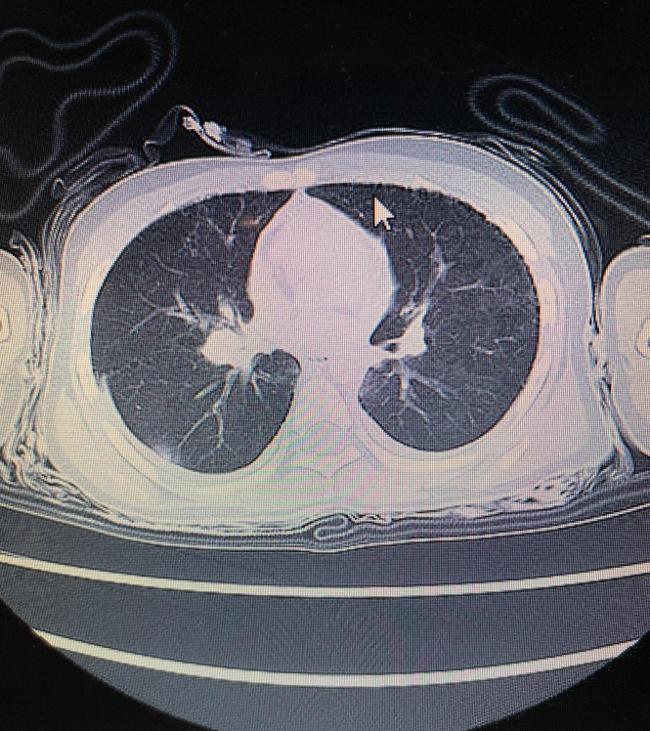

遺体の司法解剖はされなかったが、医療記録から、優空君の肺はレントゲン写真などからガラス状に映っていたことから、ほとんど肺には水が入っていないことが明らかになっている。